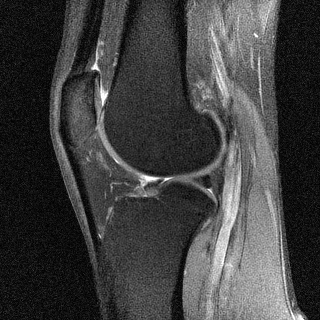

Figure 2.10: Sagittal MRI scans of the author’s knee with different contrasts. Left: T1 (TE=15 ms and TR=517 ms). Right: spin density (TE=11 ms and TR=2630 ms).

T1-weighted MRI images present a good contrast between fat, which appears dark, and water, which appears brighter. This type of contrast is used, for instance, in brain imaging to distinguish gray matter from white matter. Pathologies are often revealed by T2-weighted MRI. Edemas (abnormal accumulation of fluids) appear bright, while tumors often appear darker than normal tissues.

Examples of T1 and spin-density weighted images are shown in Figure 2.10.